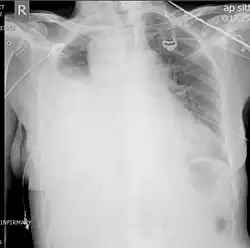

A chest X-ray is the most common technique used to diagnosis a hemothorax.[23] X-rays should ideally be taken in an upright position (an erect chest X-ray), but may be performed with the person lying on their back (supine) if an erect chest X-ray is not feasible. On an erect chest X-ray, a hemothorax is suggested by blunting of the costophrenic angle or partial or complete opacification of the affected half of the thorax. On a supine film the blood tends to layer in the pleural space, but can be appreciated as a haziness of one half of the thorax relative to the other.[5] A small hemothorax may be missed on a chest X-ray as several hundred milliliters of blood can be hidden by the diaphragm and abdominal viscera on an erect film. Supine X-rays are even less sensitive and as much as one liter of blood can be missed on a supine film.[24]

Ultrasonography may be used to detect hemothorax and other pleural effusions. This technique is of particular use in the critical care and trauma settings as it provides rapid, reliable results at the bedside.[23] Ultrasound is more sensitive than chest x-ray in detecting hemothorax.[25] Ultrasound can cause issues in people who are morbidly obese or have subcutaneous emphysema. When CT is unavailable in the current setting or the person cannot be moved to the scan, ultrasound is used.[3]

Computed tomography (CT or CAT) scans may be useful for diagnosing retained hemothorax as this form of imaging can detect much smaller amounts of fluid than a plain chest X-ray. However, CT is less used as a primary means of diagnosis within the trauma setting, as these scans require a critically ill person to be transported to a scanner, are slower, and require the subject to remain supine.[23][26]

Magnetic resonance imaging (MRI) can be used to differentiate between a hemothorax and other forms of pleural effusion, and can suggest how long the hemothorax has been present for. Fresh blood can be seen as a fluid with low T1 but high T2 signals, while blood that has been present for more than a few hours displays both low T1 and T2 signals.[27] MRI is used infrequently in the trauma setting due to the prolonged time required to perform an MRI, and the deterioration in image quality that occurs with motion.[22]